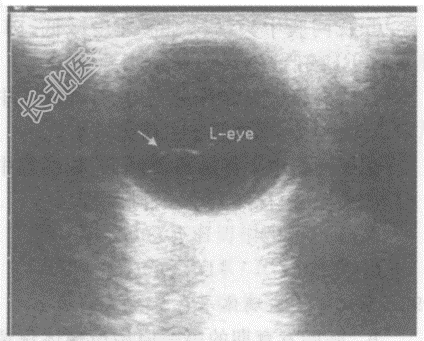

- 单项选择题男,52岁, 自述双眼前有漂浮物(飞蚊症),视力下降半年余。超声综合描述: 玻璃体内可见点状中等回声,不与球壁相连, 随眼球运动而移动。超声提示:

B、玻璃体混浊